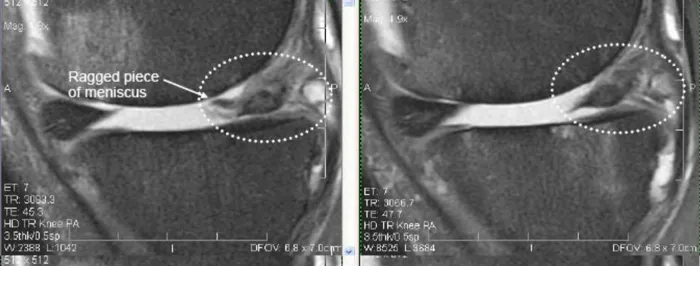

Knee – Meniscus Injuries

These are examples of patients who instead of having a meniscoctomy chose to have a precise injection of their own bone marrow concentrate, which contained their stem cells, into the meniscus.